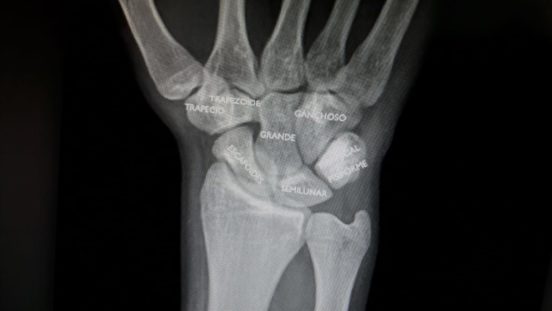

Identificación de los huesos del carpo